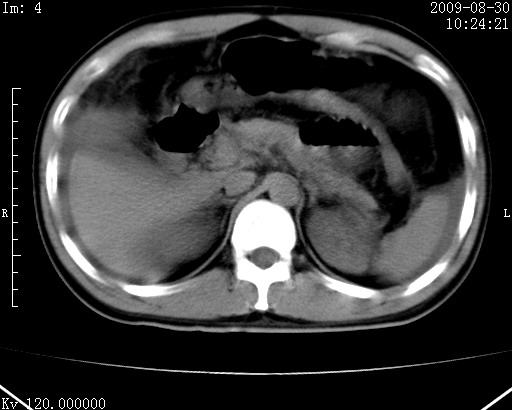

患者唐某,男31岁,已婚,本地务农。

自述入院前两天一次进食较多冷饮之后,出现阵发性上腹部疼痛,次日加剧伴恶心、呕吐,呕吐后症状稍减轻。食欲差。大便每天1-2次,量少,暗红色水样。小便赤。无畏寒、发热、咳嗽等呼吸道症状。无高血压及胃病史。

检查:体温、血压及脉搏正常.皮肤无黄染,浅表无淋巴结肿大。左腹肌紧张,左上腹有压痛,无反跳痛,可触及包块。

生化:钾、钠、氯、钙、ph正常,总胆红素和直接胆红素稍高,空腹血糖稍高。

尿淀粉酶:1256 u/l(正常60-401)。

血常规:wbc 22.4x109/l gr88% ly9.6%其余基本正常。

胃镜:急性胃炎。立位腹平片:未见异常。

下面是ct平扫,降结肠内是对比剂。

术前影像诊断:上段空肠急性缺血性坏死并腹水。建议手术治疗。

术中见上段空肠约70cm长范围坏死,从屈氏韧带远端约10cm处开始。坏死肠管肿胀变形变色,管壁明显环形增厚,部分聚成大肿块,无扭转和套叠。肠系膜上动脉分支内广泛泥沙状血栓。肠切除。

临床诊断:肠系膜上动脉梗塞并急性肠坏死。

开始时我们科也有人认为是套叠,最后统一意见,不考虑肠套。我们看到的“靶征”,“晕圈征”,“双圈征”实际上只是单根肠管的横断面。坏死肿胀后肠壁各层的密度不一样。

左侧腹小肠腔管壁明显增厚,部分内示靶征,走行异常,部分肠系膜绳样改变,肝包膜下及肠间较多液体密度,然梗阻近端肠腔积气不明显。

考虑;肠扭曲伴肠坏死。

腹部肠管肠管弥漫性增厚、肿胀,考虑为肠管缺血或淤血改变,未排除空肠管坏死。腹水。

有结果了,回顾分析,套叠只会在局部出现同心圆征,不会很长一段肠管都有,还是水肿坏死。